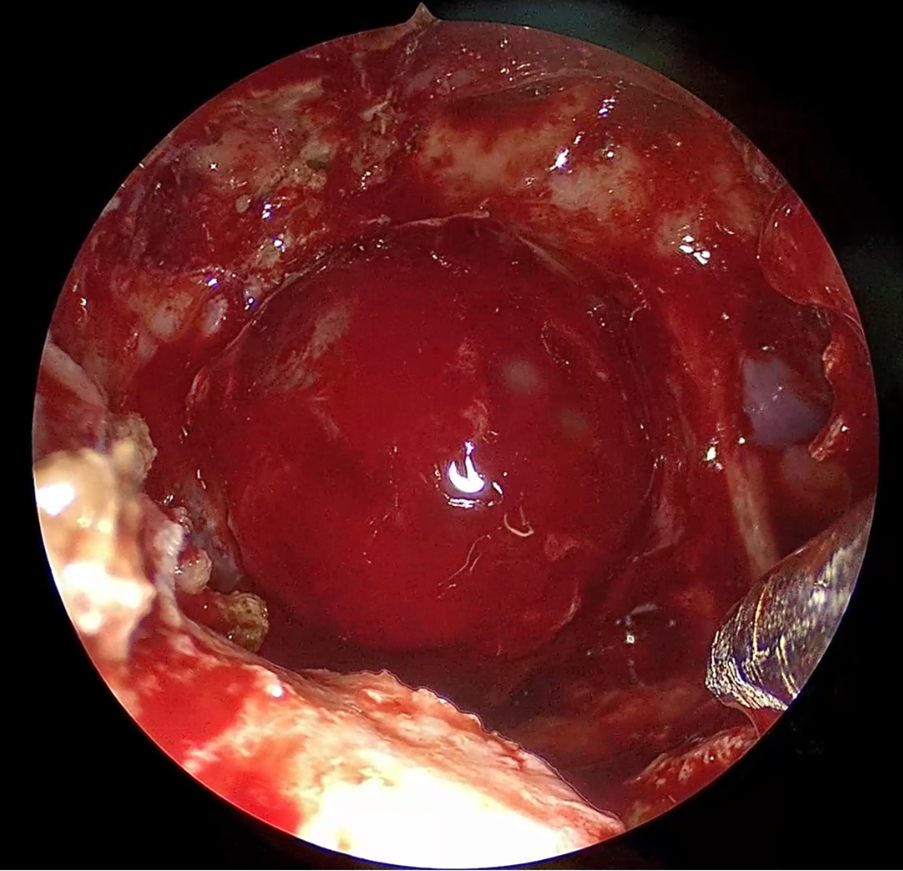

При вскрытии твёрдой мозговой оболочки в режиме монохрома и в режимах наложения мы смогли визуализировать пробег мелких сосудов опухоли, таким образом нам удалось достичь визуализации кровоснабжения опухоли.

👇 Листайте галерею влево.

По мере удаления опухоли (опухоль распространялась в правый кавернозный синус), войдя в правый кавернозный синус, следуя за опухолью, у нас была возможность, осуществить повторное введение индоцианина зелёного для идентификации пробега интракавернозного сегмента внутренней сонной артерии, который был виден не полностью, однако этого нам было достаточно, чтобы понимать, в каких пространствах кавернозного синуса мы находимся. Также в монохромном режиме у нас сохранялась возможность манипулировать и продолжить удалять опухоль, т. к. мы очень четко видели границу кавернозного сегмента внутренней сонной артерии.

После удаления опухоли, поскольку опухоль была крупных размеров, сформировалась большое резервное пространство в ложе удаленной опухоли, и в левых верхних отделах турецкого седла, значимо расширенного, мы увидели небольшой фрагмент ткани, которая при обычном свете, при обычной эндоскопической картине, напоминала здоровую ткань аденогипофиза.

Специалисты в эндоскопической гипофизарной хирургии, подтвердят, что нередко возникает вопрос, а что осталось, чему соответствует эта остаточная ткань, которую мы порой видим в различных отделах турецкого седла? Здоровая это ткань гипофиза или остаточная ткань опухоли? И порой принять решение бывает достаточно сложно, потому что, если оставить опухолевую ткань, то удаление будет не радикальным. С другой стороны, в стремлении удалить опухоль радикально, можно удалить здоровую остаточную ткань гипофиза, тем самым обречь пациента на ещё более грубый эндокринологический дефицит и пожизненную заместительную терапию.

В случаях, когда есть сомнения относительно принадлежности ткани к опухоли или здоровой ткани использование индоцианина зелёного может помочь решить эту задачу.

Во время нашей операции данный метод позволил дифференцировать опухолевую ткань и остаточную здоровую ткань гипофиза. Соответственно, контрастирующая ткань была расценена нами как здоровая ткань гипофиза, и мы сознательно её оставили, будучи совершенно уверенными в том, что опухоль удалена, а здоровая ткань гипофиза осталась.